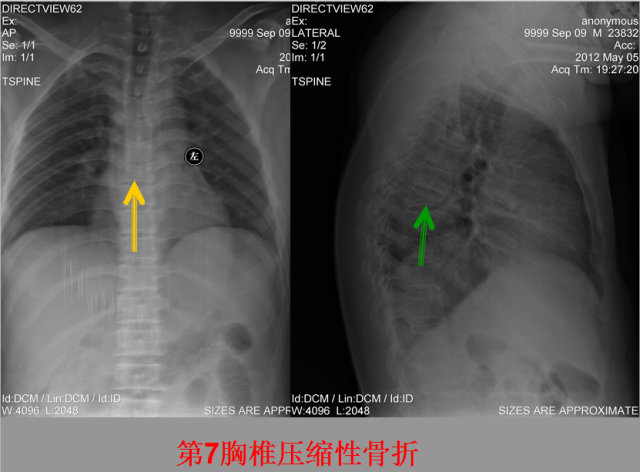

骨折篇

定义:骨折{Fracture}是指骨的完整性和连续性的折裂或粉碎。包括创伤性骨折、疲劳性骨折和病例理性骨折。 临床上以创伤性骨折*常见。